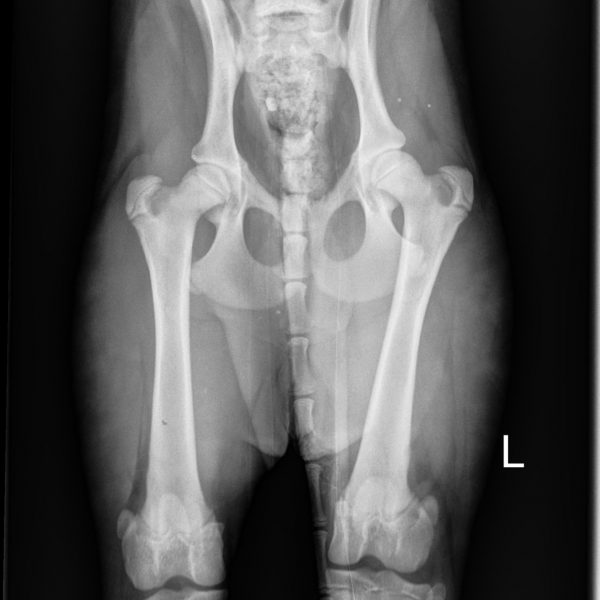

- MDBA Australian Cobberdog breeding female.

- DOB: February 13 2019.

- Height: 18 inches.

- Weight: 33 LBS.